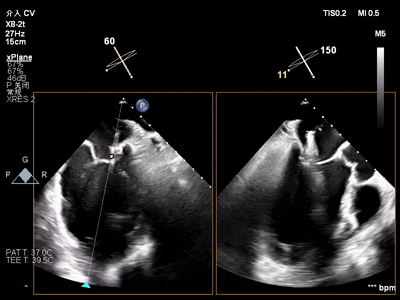

【术中操作(含关键步骤超声)】

鉴于患者术前心功能差、多支架植入的特殊情况,手术全程需兼顾“精准操作”与“保护心功能”双重要求:在全麻与经食道超声的协同引导下,团队先突破心功能受损导致的术野稳定性难题,稳步经心尖建立手术轨道与输送鞘;随后聚焦二尖瓣2偏3区精准置入一枚Ⅱf型夹合器,成功攻占这一解剖位置深、毗邻结构敏感、容错率极低而操作难度陡增的区域。

术前术后反流对比